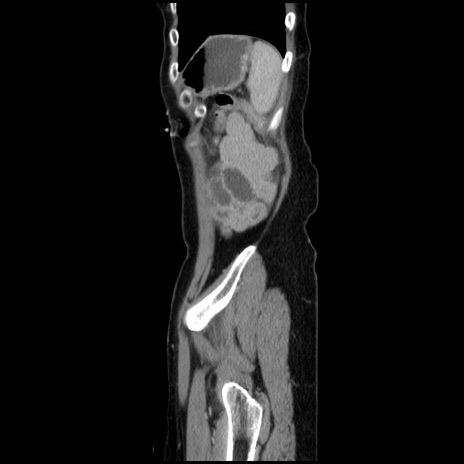

症例32(矢状断像)

【症例】40歳代 女性

【主訴】上腹部痛、嘔気・嘔吐

【現病歴】約9時間前頃から急に上腹部痛、嘔気、嘔吐が出現。改善しないため救急要請。

【既往歴】子宮頚癌(広汎子宮全摘術、放射線療法)、腸閉塞

【身体所見】腹部:平坦、軟、腸雑音亢進、上腹部を中心に腹部全体に圧痛あり。

【データ】WBC 8400、CRP 0.03